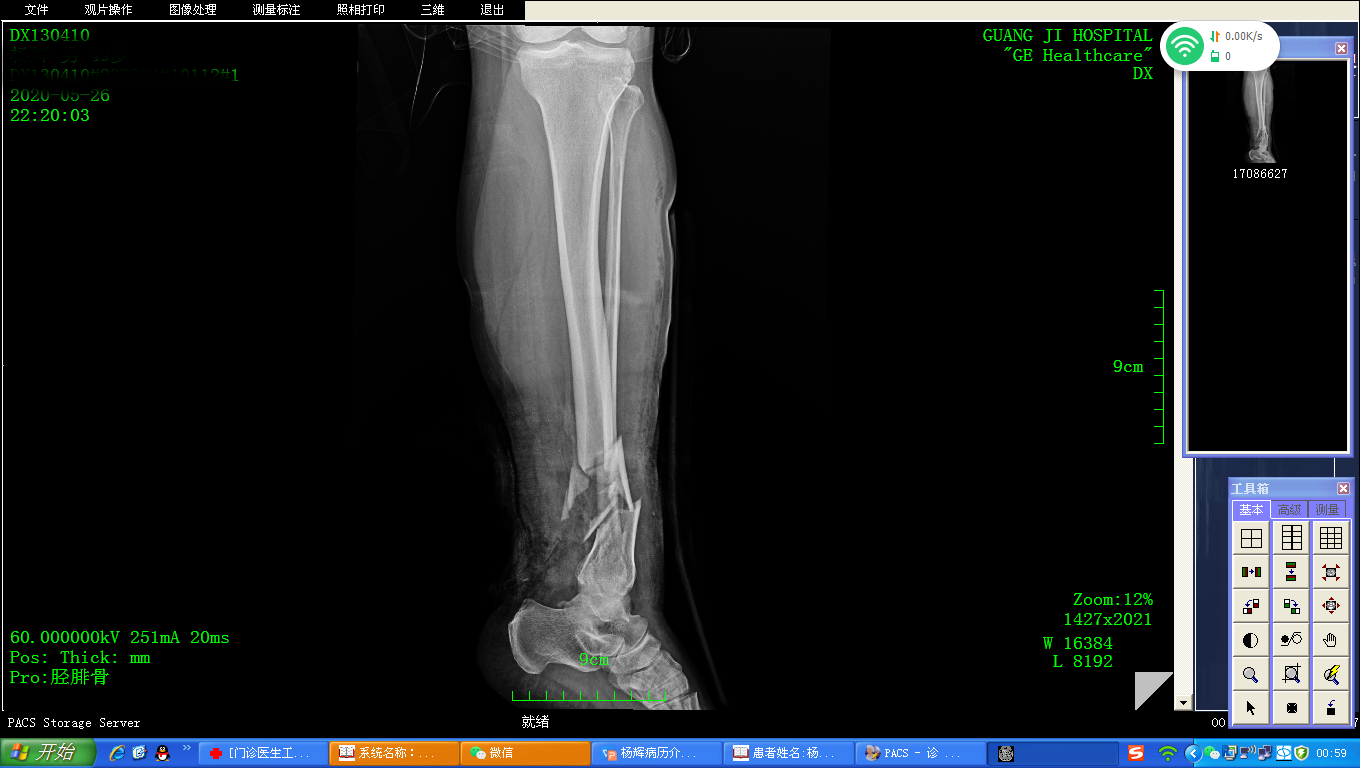

患 者:杨某,女,49岁。

主 诉:因车撞伤致左小腿疼痛出血活动受限30分钟,入院治疗。

症 见:患者30分钟前骑电动车不慎被大货车撞伤,致左小腿疼痛出血,左踝关节活动受限,不能站立行走。当时无胸闷气促,无恶心呕吐。

专科检查:左小腿远端内侧约10cmX6cm创面,出血活跃,骨质碎裂外露,污染重。左小腿后侧正中后踝近端10厘米处约5cmX3cm挫伤创面,渗血,污染重。压痛,触及骨擦感。左踝关节主动活动受限。左足肿胀瘀青,压痛,足背触及骨擦感,足背动脉未能触及。左足各趾主动活动受限。

影像资料:

诊 断:

左小腿、左足碾压伤:

1、左胫骨下段开放性骨折并骨折缺损;

2、左腓骨下段多段粉碎性骨折;

3、左跟腱止点撕脱;

4、左小腿皮肤软组织碾挫并缺损;

5、左胫前、胫后动脉挫伤;

6、左胫后肌、趾屈肌断裂;

7、左胫神经挫伤;

8、左侧大隐静脉缺损伤;

9、左内、外踝骨折;

10、左2、3、4、5趾骨骨折;

11、左足第5趾近节骨折;

12、左小腿创面感染。